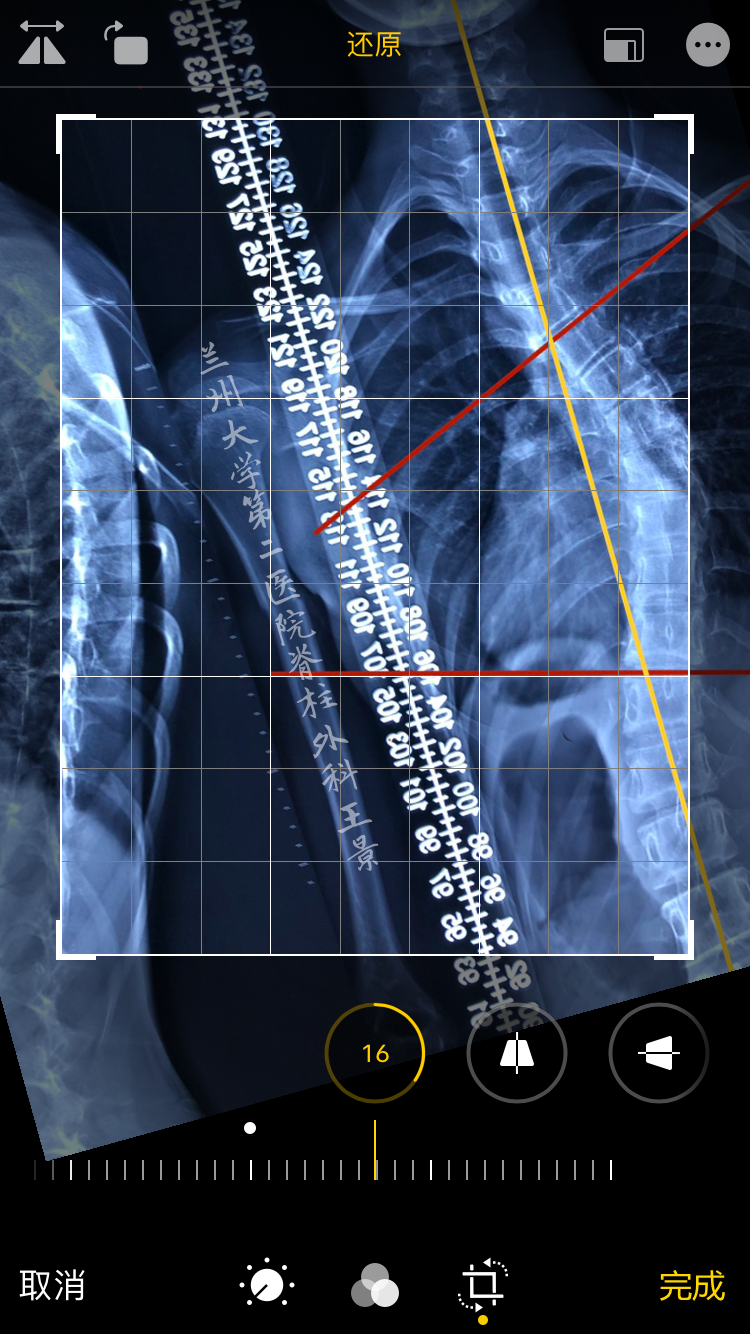

对着同一张片子

掏出iPhone,尽量正对拍摄

实际上稍微歪一点也没关系

打开照片,进入编辑模式

手指按着屏幕旋转照片

iOS自带的功能

图片旋转时会显示网格线及旋转角度

顺时针/逆时针旋转分别显示±°

精度为1°

如图所示旋转照片

如法炮制,拍照测量脊柱侧弯Cobb角

为方便演示,照片标注上、下端椎终板连线

旋转照片使终板连线和网格线重叠

读出上、下端椎的倾角绝对值

相加后就是Cobb角

这就叫

端椎倾角法快速测量Cobb角